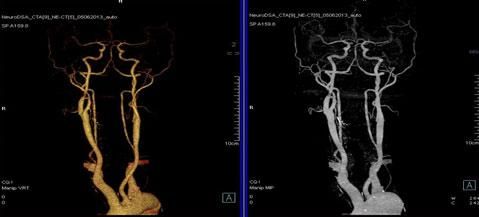

二、多層螺旋CT頭頸部及體部血管成像技術:

該機掃描覆蓋範圍廣、時間短,多種後處理分析軟件能顯示各血管細小分支,可以清晰顯示動脈瘤、動脈夾層、血管畸形、血管狹窄及動脈粥樣硬化斑塊等,适用于頭頸部血管成像、肺動脈成像、胸腹部血管成像及四肢血管成像。

1.顱腦血管成像:

動脈瘤